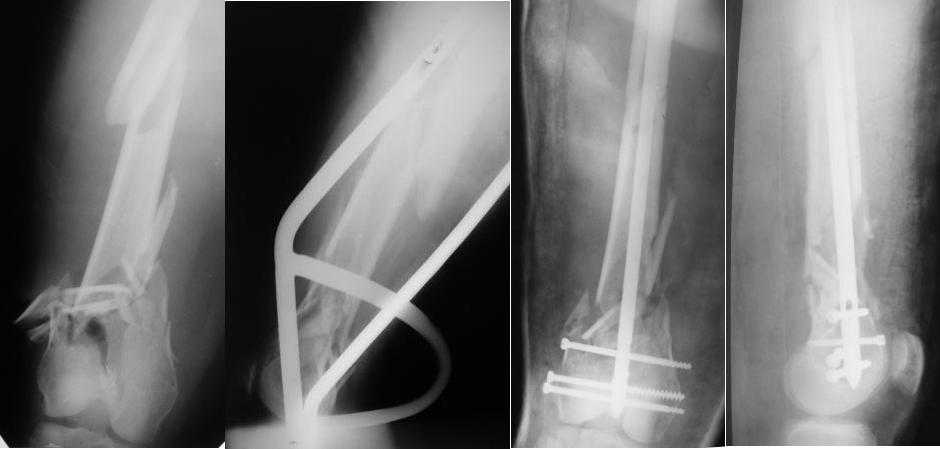

Re: Многооскольчатый перелом бедра

Какой смысл использовать тибиальный стержень на бедре?

И вообще мне кажется, что представленный ОС не допустим:1. стержень в суставе,2. неправильная длинна винтов, 3. ось конечности неправильная, 4. циркулярная гипсовая повязка после ОС?????

-1. стержень в суставе,

Это не критично, в межмышелковой борозде,не на опроной поверхности, выступает из субхондральной кости, не факт что из хряща.Про надколенник Александр Николаевич уже писал.

-2. неправильная длинна винтов,

и толщина тоже. При такой длине хочется помощнее.

-3. ось конечности неправильная,

Вполне прилично. Если в боковой проекции рекувации нет. Где кстати боковая, хочется спросить у постмейкера.

- 4. циркулярная гипсовая повязка после ОС?????

К сожалению, автор умалчивает. Думается, что в данном случае можно и без гипса.

Затем, что результаты как минимум не хуже, чем при использовании глубокоспециализированных DFN. Другое дело, что найти толстый тибиальный гвоздь больше 11м не всегда просто. В показаном примере он бы не подошел. Трочал бы сильнее из колена или при полном погружении отверстия пролетели бы проксимальнее перелома. Он показан больше для нижней трети, чем для области метафиза. Да и желательно чтобы винты толстые были, толще чем для тибии.

2. Лучше борется с рекурвацией дистального отломка за счет угла Герцога.(В представленном примере "недопобороли")

В данном случае, на мой взгляд, если говорить о гвоздях, предпочтительней антеградное штифтование. Поскольку любая ретроградная конструкция не может иметь столь низкого расположения отверстий для винтов как антеградная из-за резьбового крепления.

Приносим извенения за недостаток информации. Выкладываю все снимки. Стержень фирмы НПО ДЕОСТ(г.Пущино-на-оке)

Больная госпитализирована с тяжелой сочетанной травмой. Плюсом к перелому бедра имеется разрыв связок коленного сустава.